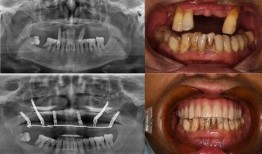

最近佛山那边的种牙事件可是闹得沸沸扬扬的,咱们得好好来聊聊这个话题。你有没有想过,一颗牙齿的种植竟然能引发这么大的波澜?那就让我...